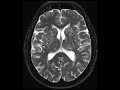

Amyloid Angiopathy

These images demonstrate innumerable foci of increased susceptibility throughout the cerebral hemispheres and cerebellum, relatively sparing the anterior frontal lobes and brainstem. These foci are associated with areas of T2 FLAIR hyperintensity and are compatible with remote microhemorrhages. The differential diagnosis includes multiple cavernomas, traumatic diffuse axonal injury, amyloid angiopathy, posterior reversible encephalopathy, and hypertensive microhemorrhages. The best diagnosis in this elderly patient is amyloid angiopathy. The parietal and occipital lobes are most commonly involved as well as the cortical and subcortical location. Lobar hemorrhage not seen here is another characteristic feature of cerebral amyloid disease.